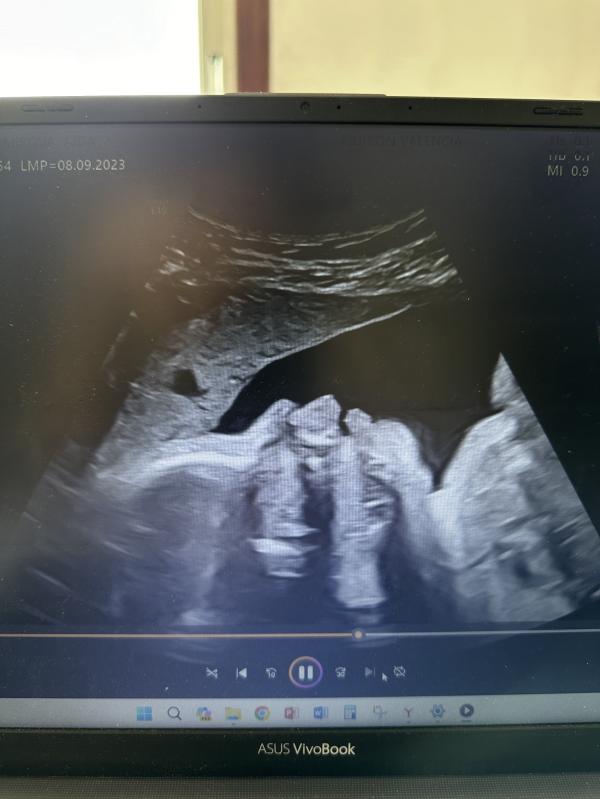

Вчера у меня был первый УЗИ скрининг за пределами Казахстана. Заранее пишу, что клиника частная в Валенсии(Испания). Зашли с мужем, так как муж немного говорит на испанском(был переводчиком). На фотографиях если заметили, то по окончанию исследования, нам выдали флешку и папку с результатами исследования с рисунками. Сегодня открыла флешку, а там оказывается запись всего исследования😍 я была приятно удивлена. Кстати, тут по умолчанию делают 3D рисунок малыша.

*также доктор провел исследование малого таза - вагинальное УЗИ. Перед этим медсестра попросила зайти в другую комнату, раздеться ниже пояса и обернуться в простыню. Тем временем медсестра уже на кушетку установила держатели ног, как в гинекологическом кабинете. И знаете мне было очень комфортно когда я была прикрыта этой простыней. Обычно в КЗ прям там же раздеваешься и просто ложишься раздвинув ноги. всегда чувствовала себя неловко, хоть и понимала, что это работа доктора и что только он/она не видела там. Отношение к пациентам ,конечно, тут совсем иное. Все такие доброжелательные, милые. Я уже распрашивала у знакомых как обстают дела в государственных больницах/поликлиниках, то ответ был такой же как у меня с частными. В государственных родильных домах очень даже хорошо относятся к роженицам и многие рекомендуют рожать там.

Наверное это уже по показаниям. Просто у меня пару дней низ живота тянуло и будто ложные схватки. Скорее всего из-за этого сделали вагинальное узи. Сказали, что всё нормально. Просто матка растягивается – растет малыш😁

За всю беременность ни разу не делали вагинально оказывается , только по животу